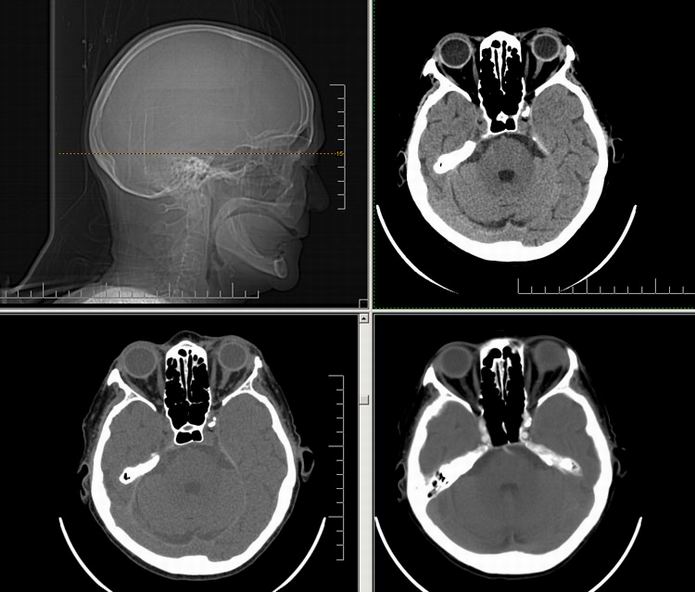

Est ce que qqun a des coupes axiales de crâne pour m'aider à réviser mon anatomie. Merci

Pour compléter tes révisions, Poupette vient de nous faire parvenir ces planches bien utiles: Planches de coupes axiales cérébrales, dans la rubrique COURS / ANATOMIE